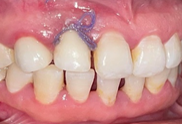

On the day of implant placement : (Figures 6,7). The implant was placed 7 years after the fall of 12 (loss of tooth due to trauma) in a completely healed site. 10 days after implant placement: (Figure 8). A temporary mesially extended bridge supported on 13 was cemented .

Figure 6 Placement of the implant + screw cover + suture.

Figure 7 Postoperative retro alveolar radiograph on the day of implant placement.

Figure 8 10 days after implant placement: removal of sutures.

6 months after implant placement: (Figure 9). A second surgical step for the placement of the healing screw to shape the soft tissue, especially the emergence profile.

Figure 9 Placement of the healing screw (6 months after osseointegration).